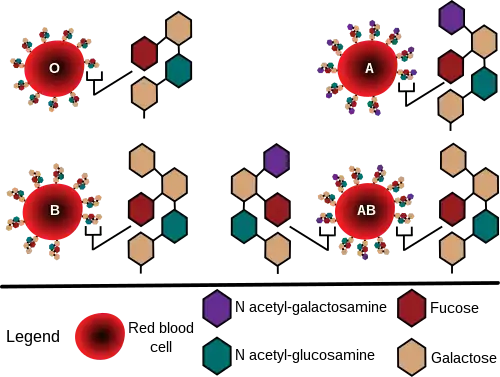

The ABO blood group system involves two antigens and two antibodies found in human blood. The two antigens are antigen A and antigen B. The two antibodies are A and B. The antigens are present on the red blood cells, and the antibodies in the serum. Regarding the antigen property of the blood, all human beings can be classified into four groups: those with antigen A (group A), those with antigen B (group B), those with both antigen A and B (group AB), and those with neither antigen (group O). The antibodies present together with the antigens are found as follows:

- Antigen A with antibody B

- Antigen B with antibody A

- Antigen AB with neither antibody A nor B

- Antigen null (group O) with both antibodies A and B